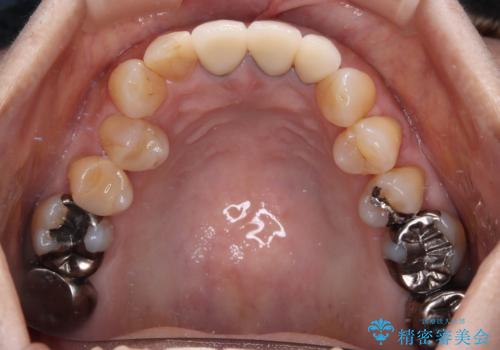

透明感のある自然な色合いとなり、患者様には大変満足していただけました。